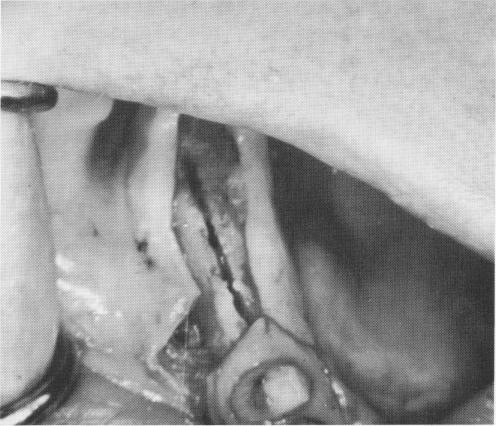

Fig. 7-40. This groove is too wide, reducing wedging action of the blade against bone.

Making the groove. The groove must be narrow and clean-cut (Fig. 7-39). If it is too wide buccolingually, the wedging action of the blade against bone is reduced (Fig. 7-40). The length of the groove should correspond to the length of the blade.